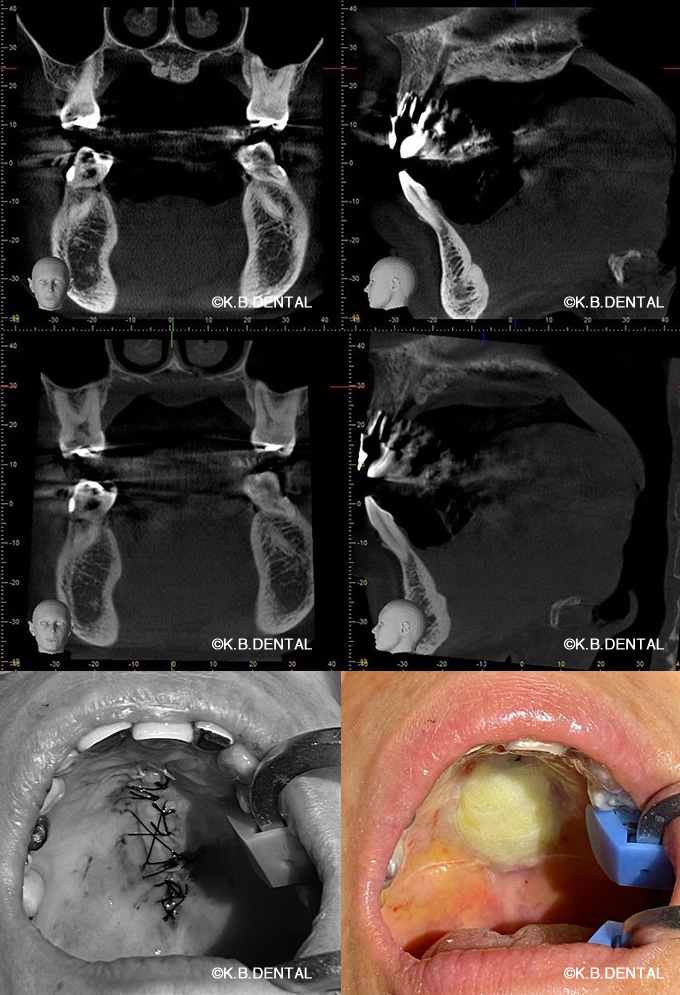

エナメル上皮腫(濾胞型)

術後2年経過の最も典型的なエナメル上皮種です。再発率が非常に高いので最低でも5年以上の経過観察が必要となります。今回は摘出術と一部健常域まで辺縁切除(骨を削る)を行いました。

1枚目(パノラマ)上:術前 下:術後 摘出部分に新生骨を認めます。

2枚目(CT)上:術前 下:術後 摘出部分に新生骨を認めます。

3枚目 左:摘出物の腫瘍本体と割断像 右:割断して内容物が充実性である事がわかります。

4枚目 上:高倍率 下:低倍率 腫瘍実質の胞巣が濾胞状を示しているのがわかります。